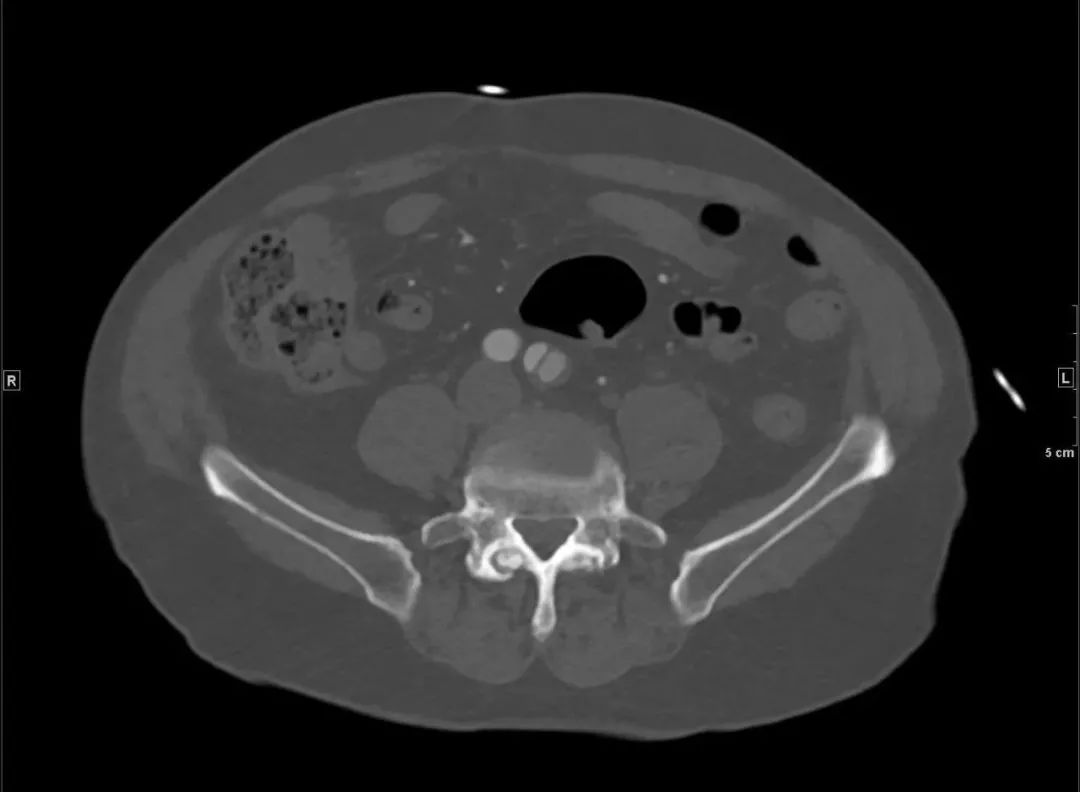

还好,那一下午人不不多,很快开申请单、登记、预约,一小时后做了胸腹盆增强CTA,当看到增强图像时,让我们倒吸一口凉气,约L1椎体水平至左侧髂总动脉夹层。患者紧急住院。

腹主动脉CTA腹腔干水平(骨窗) 左侧髂总动脉(骨窗)